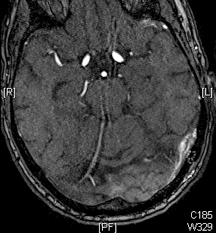

Ist eine AV-Fistel durch MRT und eine diagnostische Angiographie sicher nachgewiesen, gibt es in Abhängigkeit von der Lage und Ausdehnung der Fistel verschiedene endovaskuläre Behandlungsoptionen. Heute wird in den meisten Fällen versucht, die AV-Fistel unter Erhalt der venösen Blutleiter zu veröden (Embolisation). Hierfür wird ein sehr dünner Katheter („Mikrokatheter“) über die Leiste bis in die Fistelgefäße geführt. Dies geschieht unter Vollnarkose. Über den Katheter wird ein Embolisat in die Fistelgefäße gespritzt, um diese zu verkleben bzw. zu verstopfen. Für die Embolisation kommen verschiedene Materialien zur Anwendung, überlicherweise werden heute Flüssigembolisate verwendet. Bei ausgedehnten Fisteln kann ein Ballonkatheter über die Leistenvene in den beteiligten venösen Blutleiter in das Gehirn eingelegt werden, um die Vene während der Embolisation vor einer Verstopfung durch das Flüssigembolisat zu schützen. Je nach Größe und Lokalisation der Fistel sind mitunter mehrere Behandlungen notwendig.